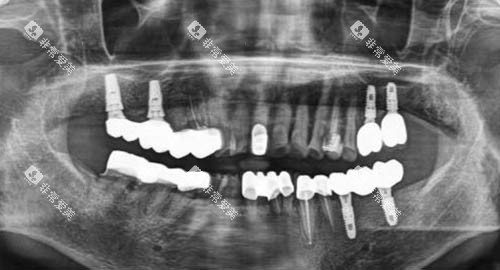

种植牙技术优质:医院汇聚了一支经验充足的种植牙团队,其中不乏海归硕士等高学历医师。

他们精通各种种植牙技术,例如 all on 6 和种植导板导航种植等。

医院采用德国进口种植体和全智能化种植技术,不仅能有效降低创伤,还能缩短修复时间。